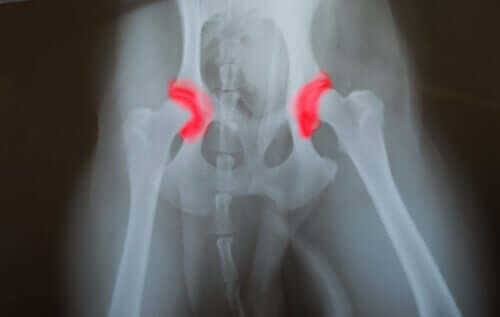

고관절 이형성증이란?

고관절 이형성증이나 팔꿈치 이형성증은 세대를 거듭하여 발병하는 유전성 질환이다. 고관절이든 팔꿈치 관절이든, 관절을 형성하는 뼈들이 바른 위치에 있지 않거나 정렬되지 않아서 발병한다.

이형성증이 생기면 관절끼리 마찰하고 움직임에 문제가 생겨 마모를 촉진한다. 그리고 이는 관절이 제 기능을 못해서 생기는 다른 문제로 이어진다. 고관절 이형성증의 문제는 조용히 진행된다는 것이다.

즉 오래 전부터, 심지어는 태어날 때부터 문제가 있었을 수도 있지만, 병이 진행되기 전까지는 개가 통증을 느끼지 못하는 것이다. 반려견이 밥을 먹지 않는다거나 거의 못 움직일 때가 되어서야 증상을 알아차리게 될 것이다.